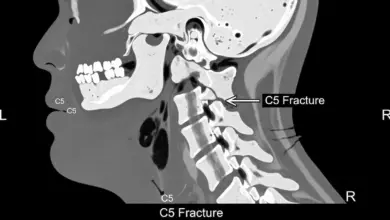

- Dor intensa após queda, acidente ou impacto.